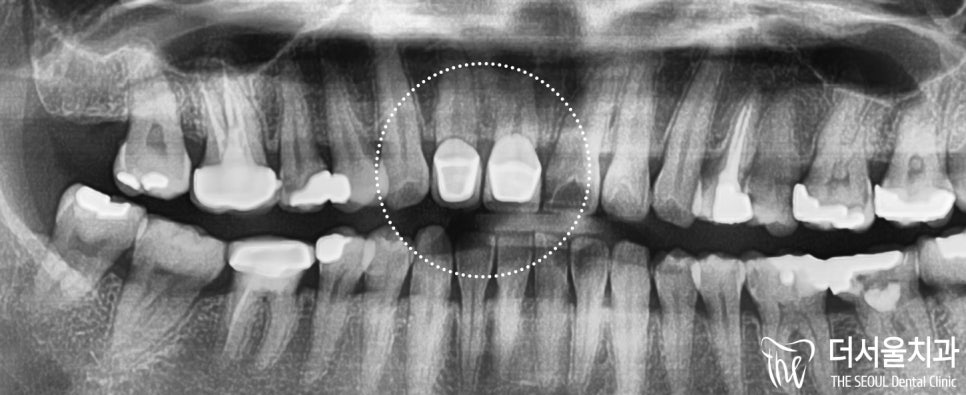

앞니 통증 때문에 더서울치과에

오신 분의 엑스레이입니다.

큰 앞니와 작은 앞니에서

통증을 느끼고 있었으며

신경치료는 되어있지 않으나,

크라운이 씌워진 것을 볼 수 있습니다.